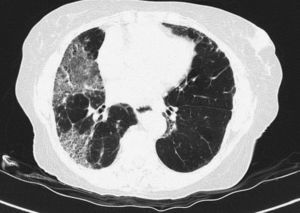

Pulmonary manifestations can be an extraglandular complication, with reported prevalence varying widely (9–75%), depending on the methods of detection and patient selection. Lung involvement (symptoms and either pulmonary function testing or radiographic abnormalities) can occur in 10–20% of patients.2 Image techniques, such as chest radiographs and high resolution computerized tomography (HRCT), are the most useful tools to detect lung involvement. A plain chest X-ray has a low sensitivity to detect early lung involvement. Studies that systematically perform HRCTs, even in asymptomatic patients, report higher rates of pulmonary abnormalities compared with studies based on clinical symptoms.3 HRCT may identify ground-glass attenuation, thin-walled cysts, honeycombing, reticular pattern, small nodules and enlarged mediastinal lymph nodes. Several histopathologic patterns have been described in PSS, including nonspecific interstitial pneumonia (NSIP), usual interstitial pneumonia (UIP), organizing pneumonia (OP) and lymphocytic interstitial pneumonia (LIP). Most of these patterns are known as diffuse interstitial lung disease (ILD). LIP has a typical radiographic appearance in ground glass opacities with thin-walled cysts, and the presence of these cysts on HRCT scan should raise clinical suspicion for PSS with ILD.4,5

NSIP is the most commonly observed histopathological pattern in connective tissue diseases with ILD, including PSS. In patients with PSS and ILD, HRCT and histopathological findings are well correlated6 and a lung biopsy is usually not recommended. However, radiographic features suggestive of lymphoma (consolidation, large nodules or pleural effusions) require thorough investigation7 (Figs. 1–3).